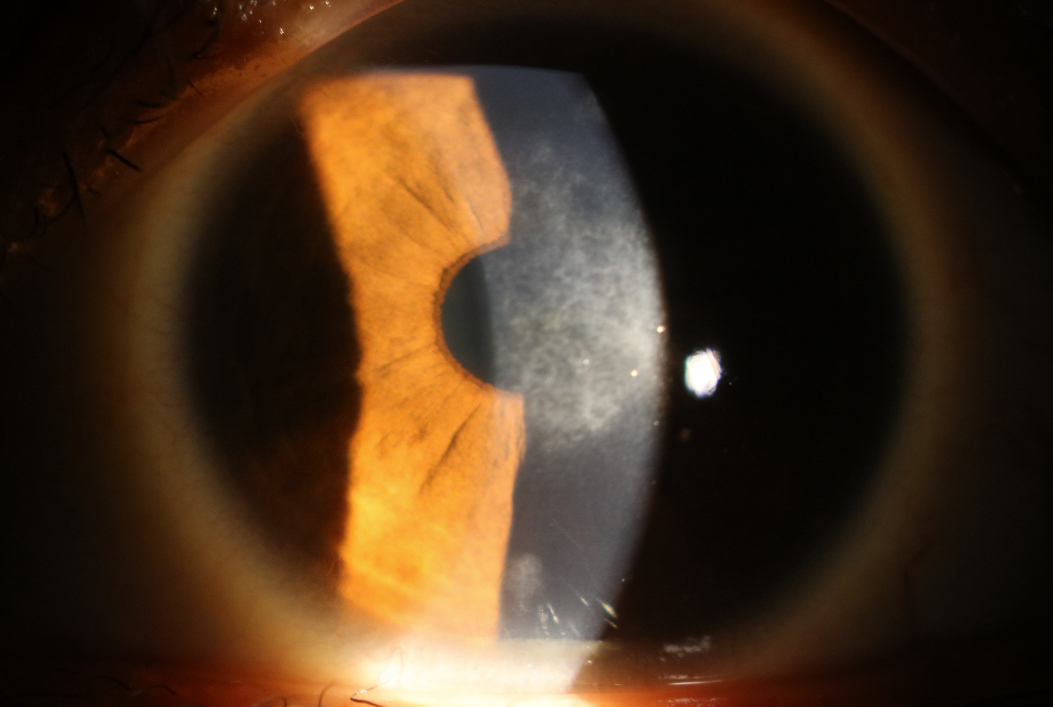

각막혼탁(corneal haze)은 수술 후 염증 반응이 조절되지 않으면, 각막의 상피 하부나 실질층에 흉터 조직이 생기며 각막이 뿌옇게 변하는 현상입니다.

이로 인해 시야가 흐려지고 빛 번짐(glare) 현상, 시력 저하가 동반될 수 있습니다.

실제 사례: 안약 중단 후 발생한 각막혼탁

이 환자는 라섹 수술 후 한 달만 항염증 안약을 사용하고 괜찮은 것 같아 스스로 중단했습니다. 하지만 6개월 후 시력이 떨어지고 뿌옇게 보이는 증상을 느껴 안과를 방문했을 때, 명확한 각막혼탁이 확인되었습니다.

[각막혼탁 실제 슬릿램프 사진]

해당 사진에서 보이는 회백색의 혼탁은, 수술 후 염증 반응이 제대로 조절되지 않아 조직이 불투명하게 된 상태입니다.